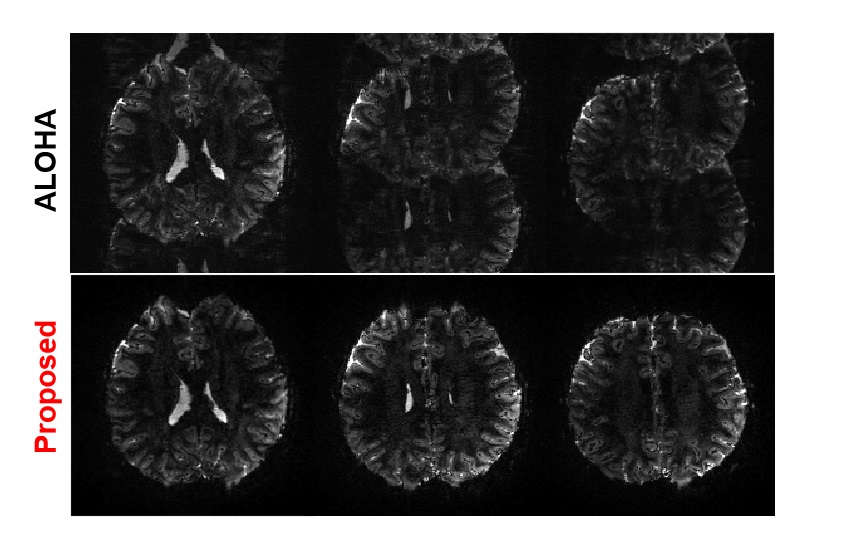

Recall that 7T EPI data is quite sensitive to the local field inhomogeneity, and the phase change is also large and nonlinear [16]. Therefore, the reference-based method which obtains a pre-scan from MR is often not able to perform the phase correction. Unlike the 3T EPI data, we found that ALOHA is not robust for 7T EPI due to the larger local field inhomogeneity variations. One could increase the matrix pencil size for the Hankel matrix to improve the performance of ALOHA, but the associated memory and computational complexity increases are sometime not acceptable in real applications. Moreover, with bigger matrix pencil size, the algorithm became more sensitive to other hyperparameters. Thus, ghost correction using ALOHA on 7T MR shows many failure cases. Specifically, from 6,250 set of slices in our experiment, we could get the only 1,346 successful cases for ghost correction using the ALOHA. Thus, only 1,346 successful cases are used as label data for our neural network training. Fig. 9 shows representative failure cases from the test data by the ALOHA-based ghost correction for 7T data. Interestingly, as shown in Fig. 9, even for the failure cases by ALOHA, the proposed method successfully corrected the ghost artifacts. In fact, among all data we used, no failure cases were observed using the proposed k𝑘k-space deep learning approach for ghost correction. This shows that the proposed algorithm is very robust even under large local field inhomogeneity changes. Even in the cases where ALOHA was successful, the proposed method mostly outperforms ALOHA as shown in fig. 5 and fig. 6. Given that CNN is closely related to ALOHA, this phenomenon may appear mysterious. However, in CNN approaches, the resulting receptive field size from the U-Net covers all image, resulting in significantly large matrix pencil size. Moreover, as discussed before in detail, despite the use of the same filter coefficients, the number of distinct basis representation increases exponentially with the depth and width thank to the combinatorial nature of ReLU [29]. This is in contrast to the data specific representation learning from Hankel matrix decomposition, which results in single linear representation. Therefore, the CNN approaches have significant advantages in terms of generalization capability and expressivity, which is not observed in the low-rank Hankel matrix decomposition.

Figure 9: Robustness of the proposed method. Even for the failure cases by ALOHA, the proposed method successfully corrected the ghost artifacts, and the proposed method was successful for all experimental cases.